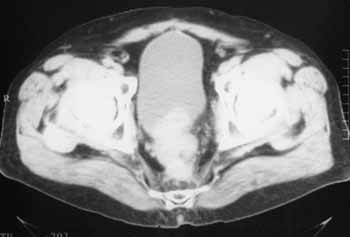

Интроскопическая диагностика рецидива рака прямой кишки.

Рис. 4. Рецидив. Выбухание рецидивных масс в просвет мочевого пузыря.